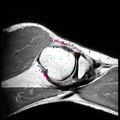

We are developing methods for segmentation of surfaces defined by polygonal meshes. In image or volume-slice segmentation, 'information' comes from image intensity, while in mesh surface segmentation the information is purely geometric. The goal of this project is to develop algorithms allowing a user to quickly and robustly segment one or several regions on a surface.

Added structs for encapsulating and visualizing sparse-field layers, example visualization on torus test-case shown. Allows better user feedback and interactivity than previous triangle-based view.